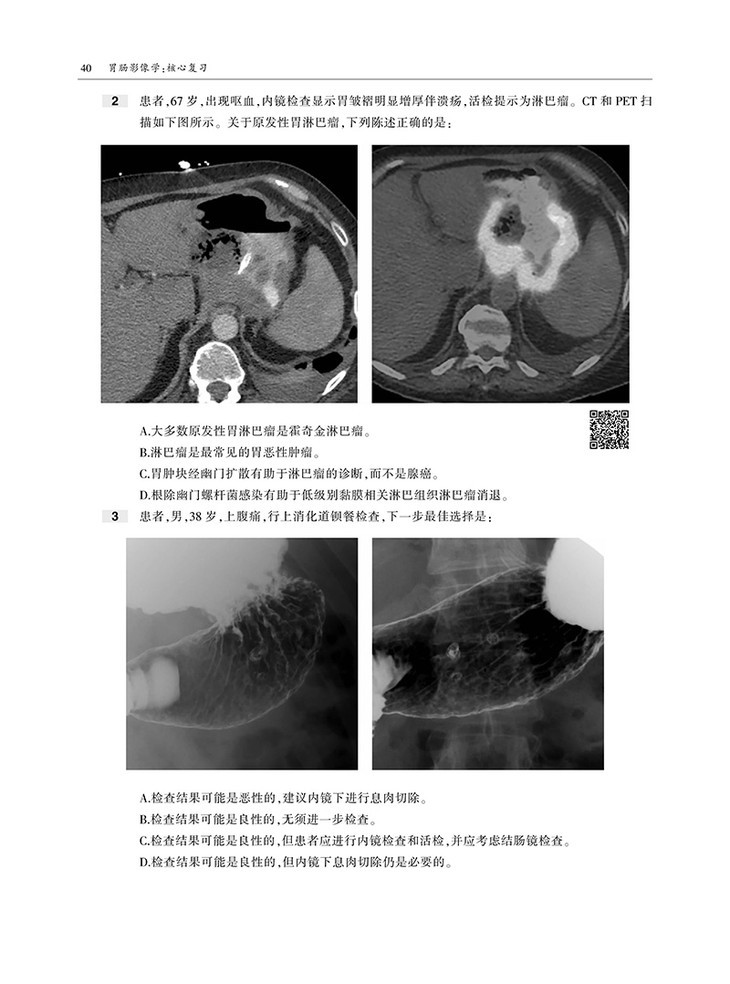

本书内容采用问答体例,首先给出患者病史和影像图片,然后列出问题和选项,便于读者独立思考,选择答案。各章末附有选择题答案和解析,正确选项和错误选项均有详细的注释,有助于读者加深理解和记忆。

囊括数百幅高清图像,直观显示病变的形态与特点等。